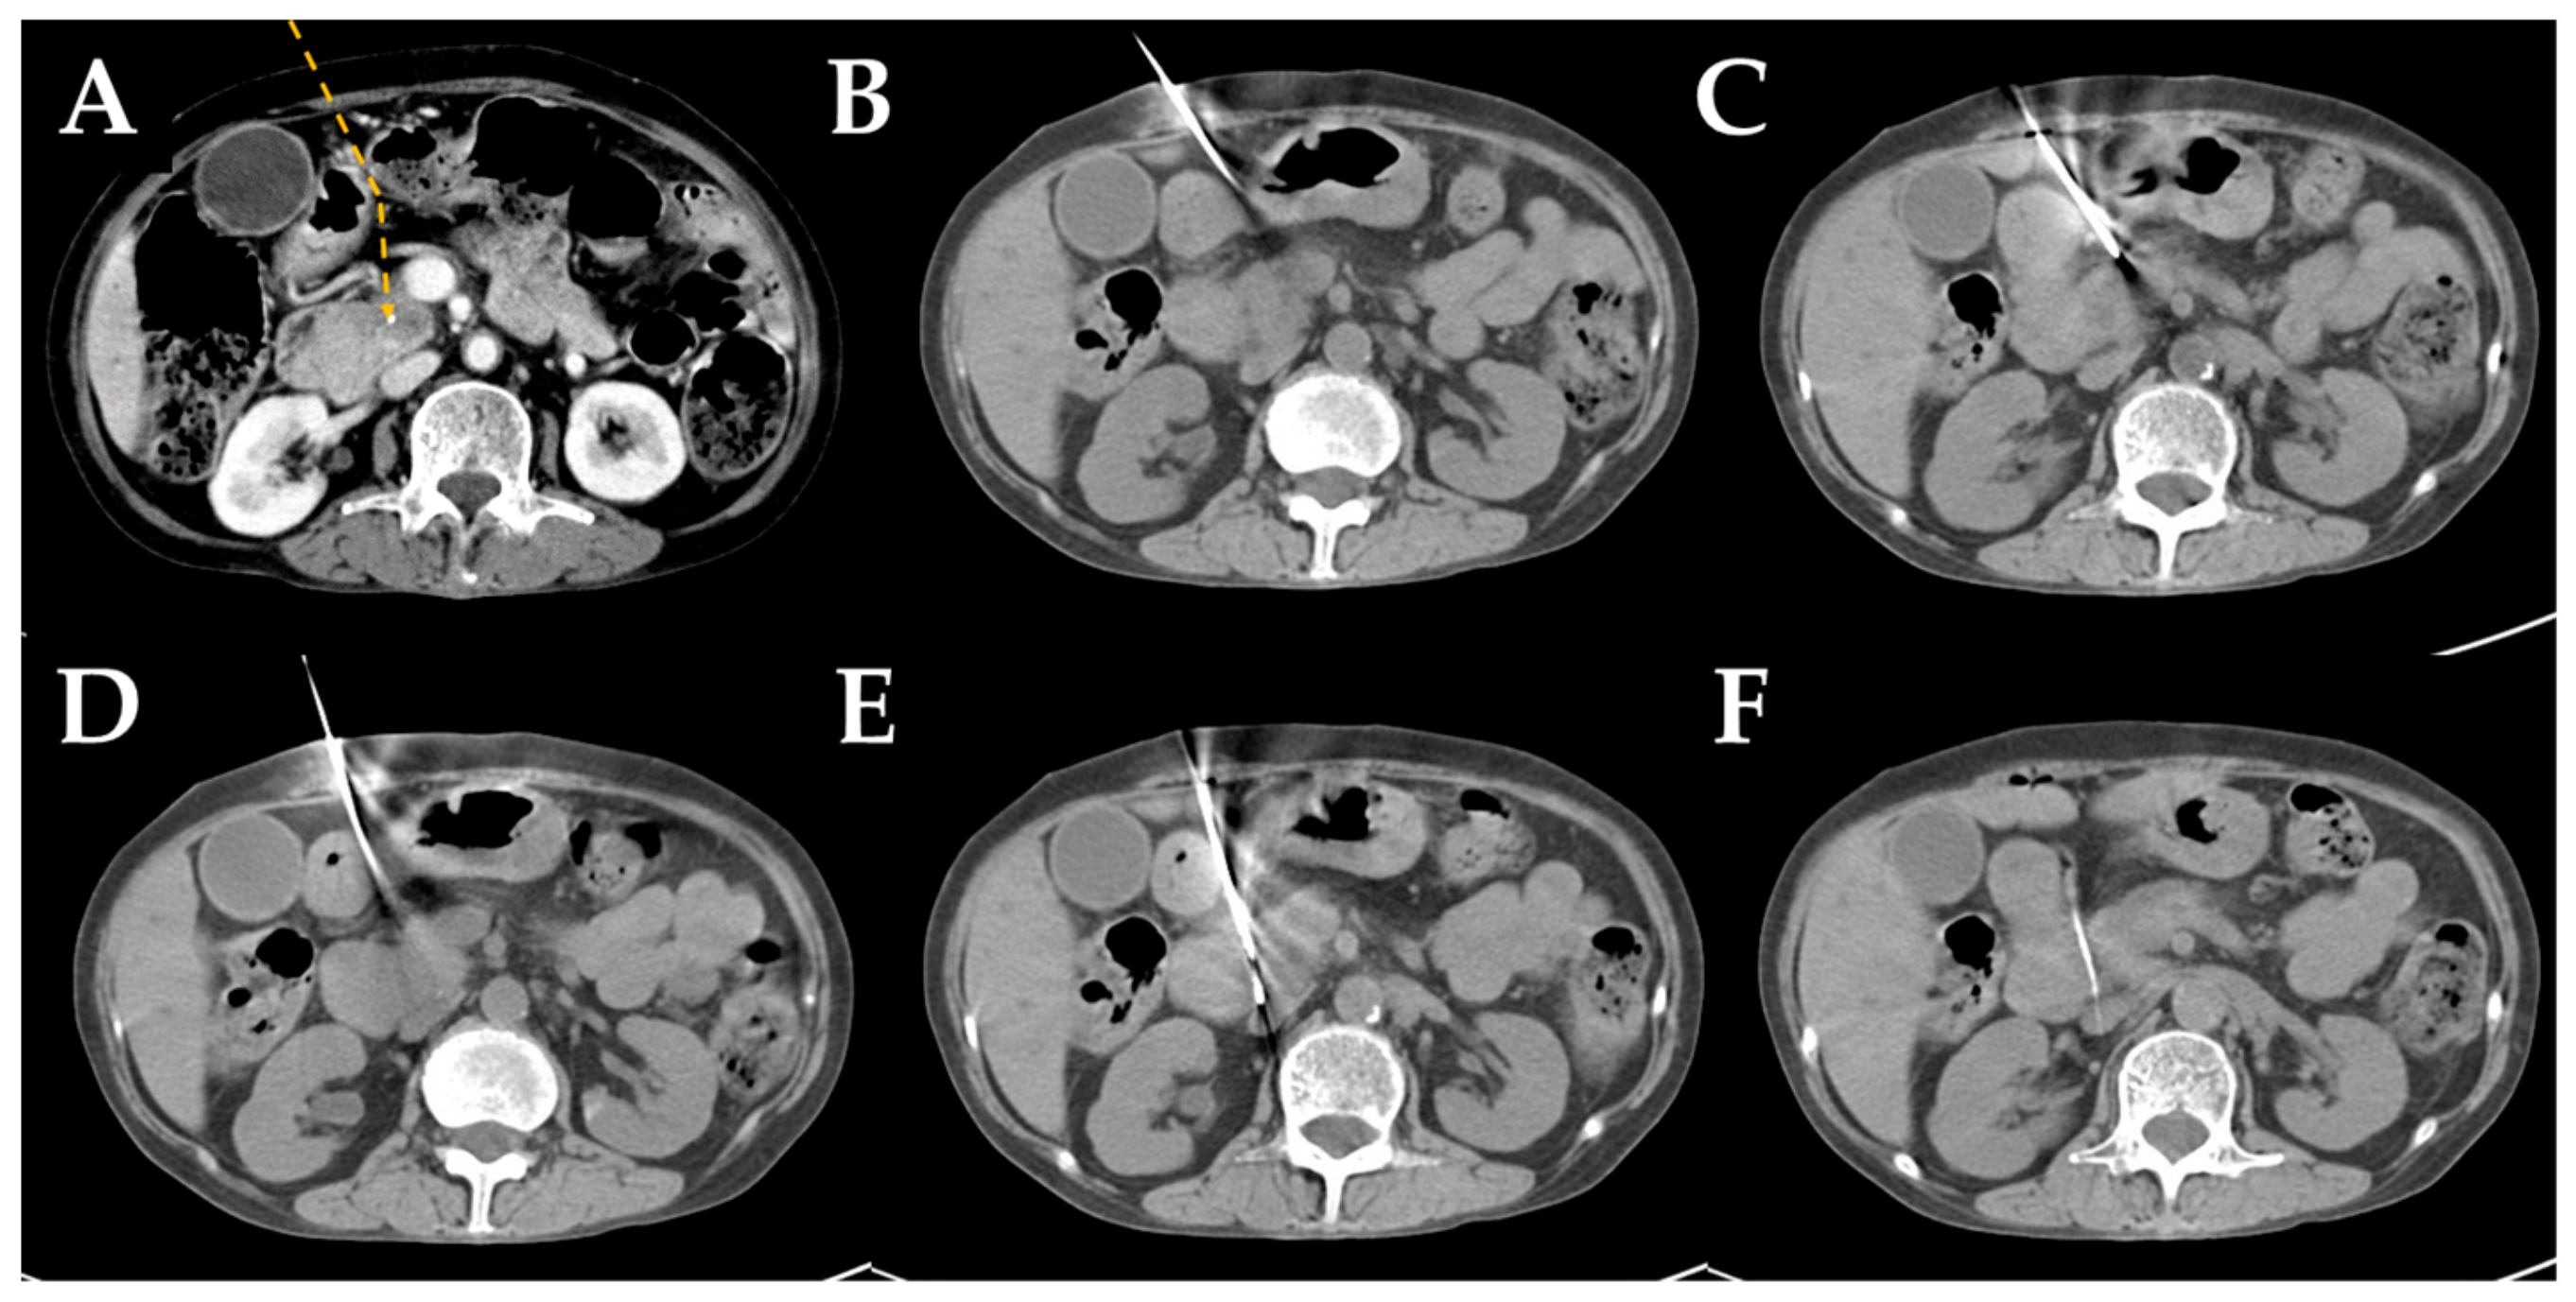

2.2. Computed Tomography-Guided Core Needle Biopsy Technique

| Detour route 1 | 169 | 29 (14–54) |

| Detour route 2 | 169 | 28 (12–51) |

| Detour route 3 | 26 | 28.5 (17–42) |

| Detour route 4 | 19 | 29 (16–41) |

| Detour route 5 | 26 | 29.5 (19–40) |

| Detour route 6 | 11 | 28 (19–38) |

| Detour route 1 | 26 | 49 | 43 | 51 | 169 (40.2%) |

| Detour route 2 | 16 | 32 | 39 | 82 | 169 (40.2%) |

| Detour route 3 | 2 | 4 | 3 | 17 | 26 (6.2%) |

| Detour route 4 | 0 | 2 | 6 | 11 | 19 (4.5%) |

| Detour route 5 | 3 | 10 | 6 | 7 | 26 (6.2%) |

| Detour route 6 | 0 | 6 | 2 | 3 | 11 (2.6%) |